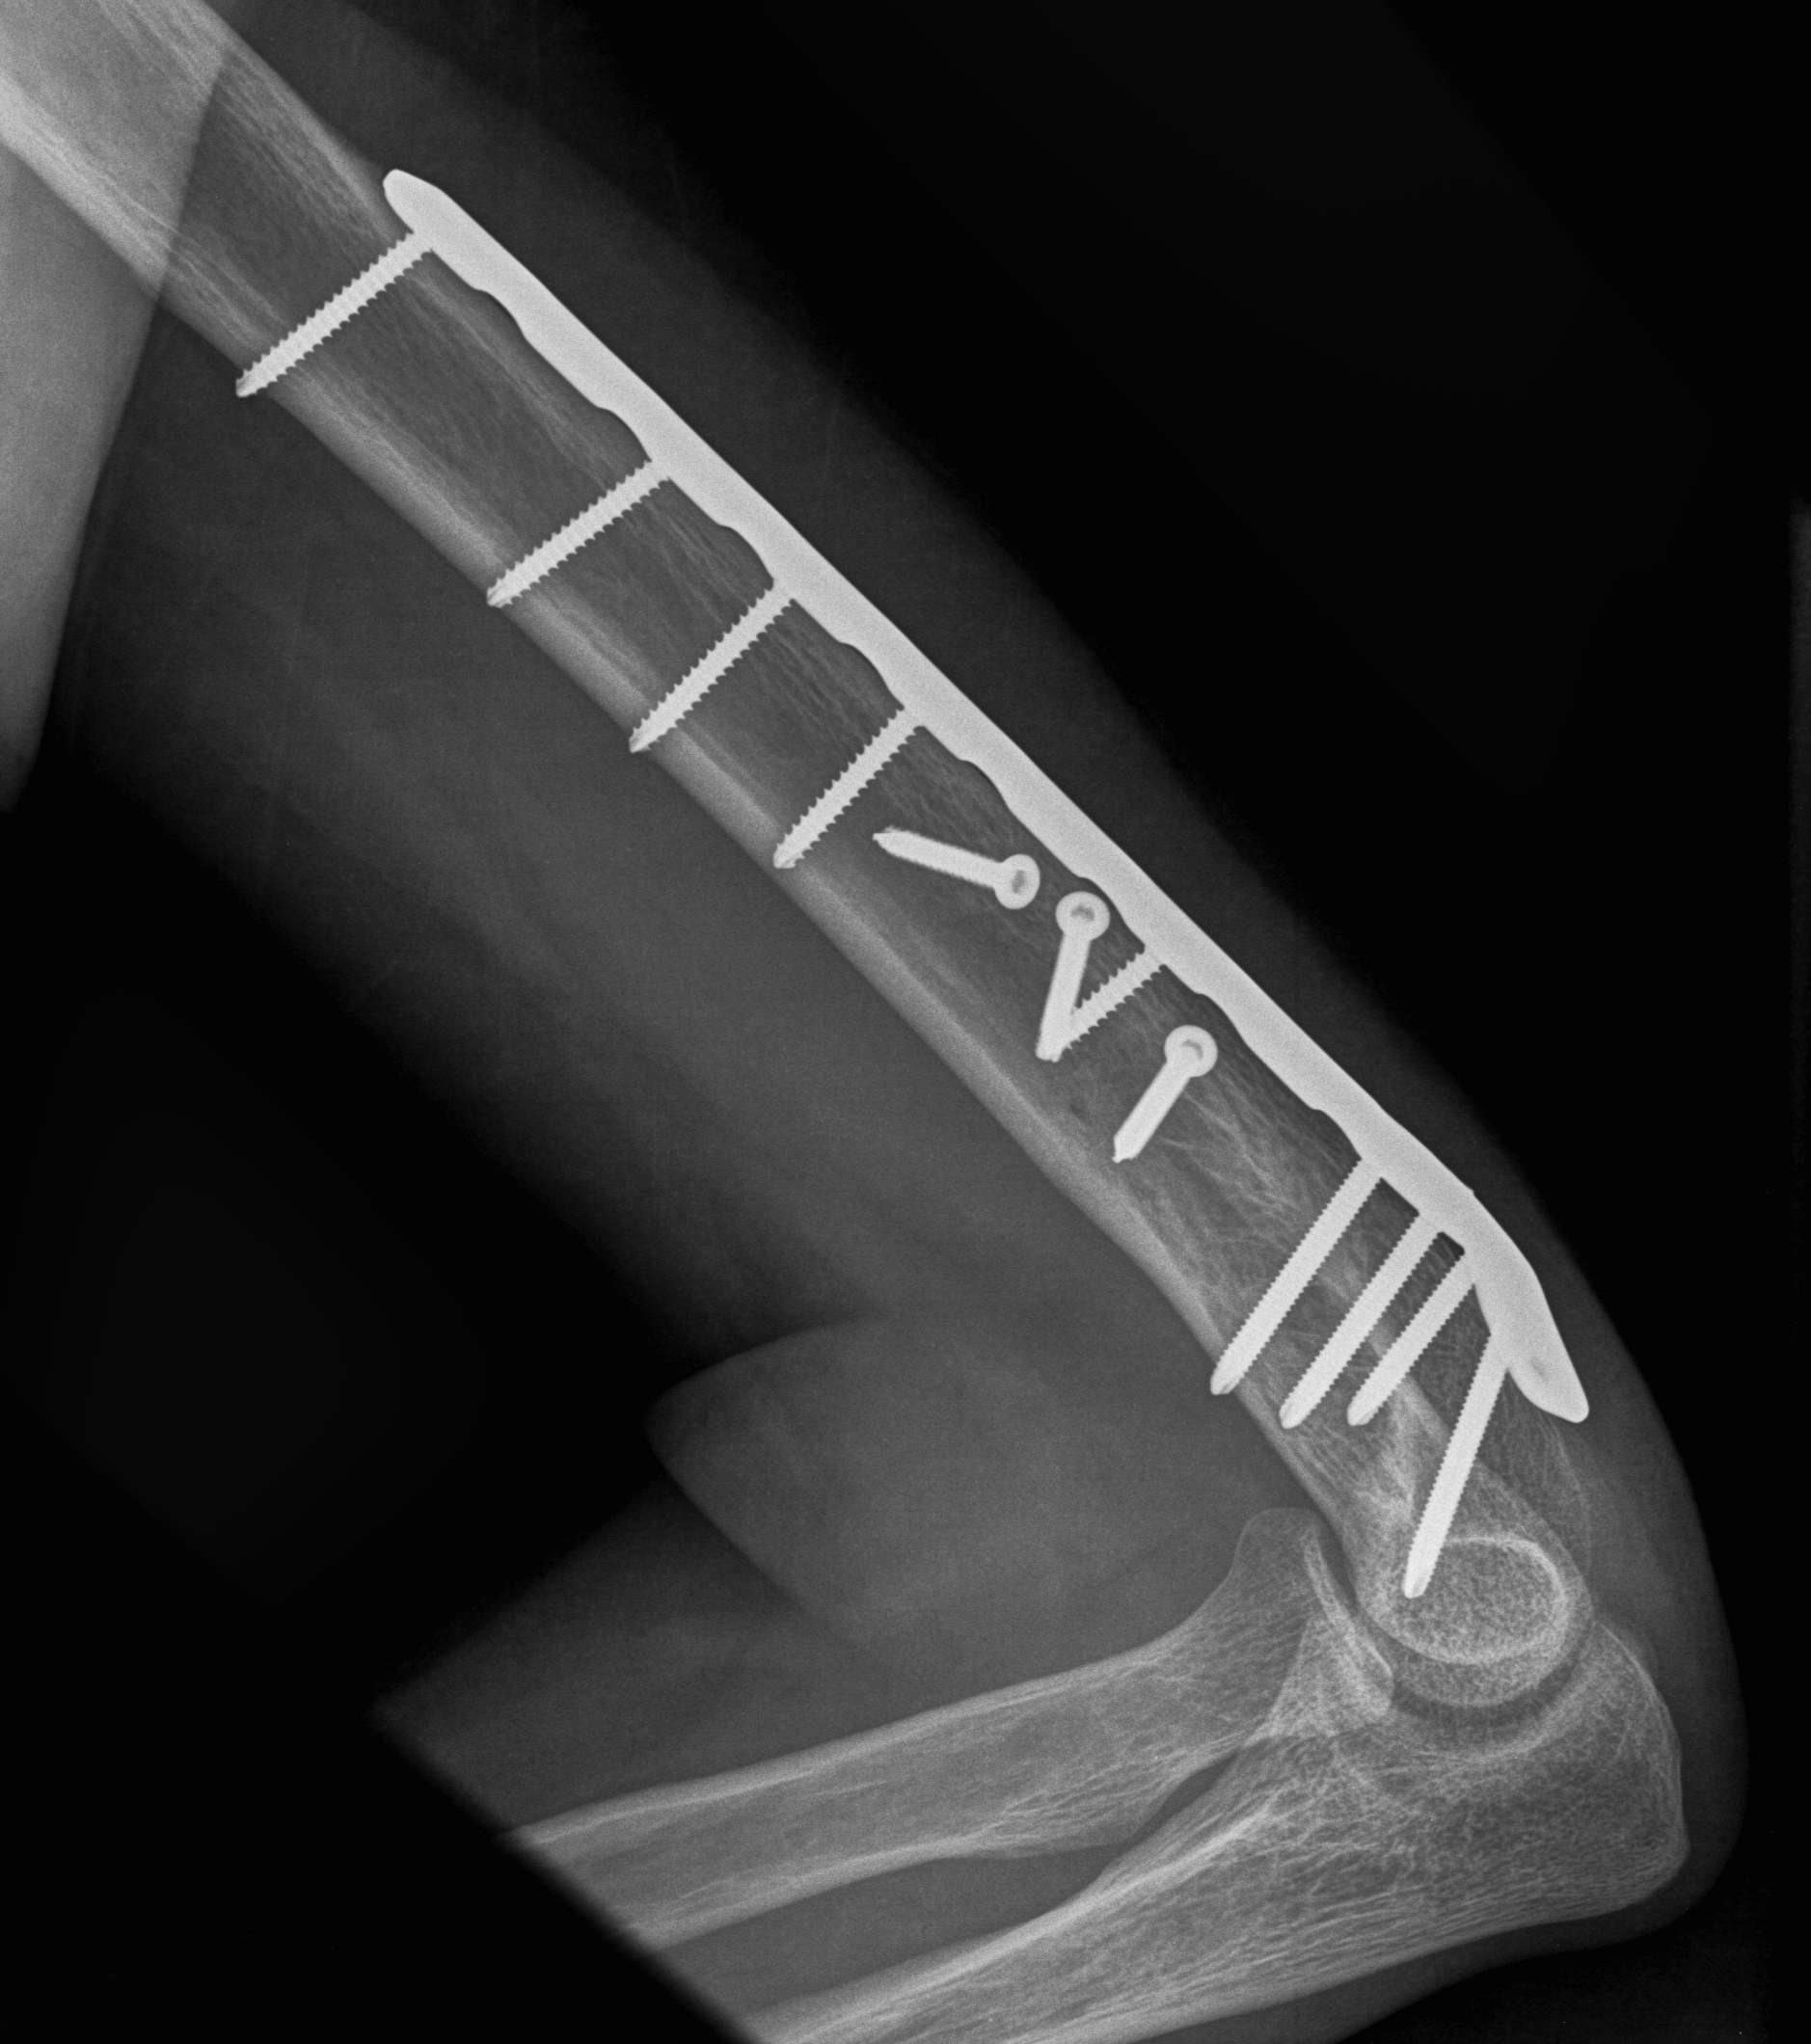

Humeral Fracture SegmentalHumeral Plate LateralHumeral Plate Long AP

Segmental fracture ORIF